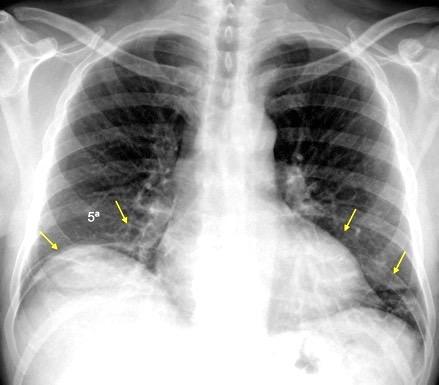

Nódulos pulmonares múltiples. (flechas verdes). Masas paratraqueales. (flechas amarillas). Dudoso ensanchamiento retrocrural (flechas negras). sigue….

Ttawfik A et al. Trans-diaphragmatic Pathologies: Anatomical Background and Spread of Disease on cross-sectional Imaging. Current Problems in Diagnostic Radiology. 2021.

T. mixto de células germinales del testículo

izquierdo Metástasis pulmonares. (flechas verdes). Ganglios paratraqueales. (flechas amarillas). Ganglios retroperitoneales (flechas negras)

Tawfik A et al. Trans-diaphragmatic Pathologies: Anatomical Background and Spread of Disease on cross-sectional Imaging. Current Problems in Diagnostic Radiology. 2021.